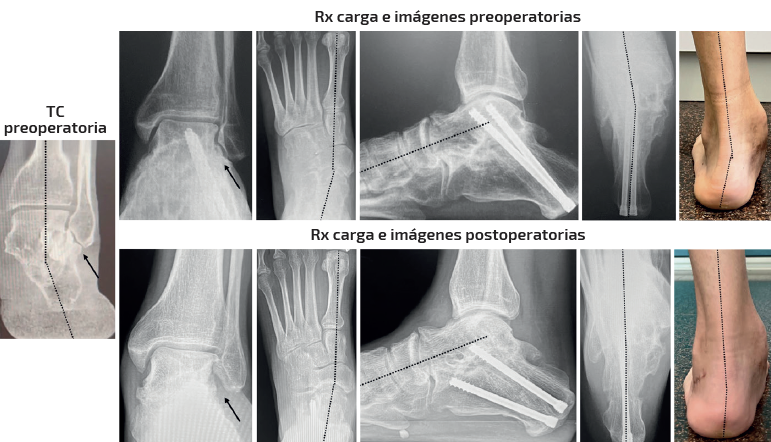

Caso 4 (Figura 7)

Se trata de una paciente mujer de 16 años. Afecta de coalición talocalcánea ósea con deformidad en valgo y abducto con subtalar rígida. Dolor medial y en sinus tarsi. Tipo IIB de Myerson. Tratamiento: osteotomía de alargamiento de la columna externa en el calcáneo y osteotomía pronadora según Cotton + alargamiento del tríceps sural según Strayer. Aloinjerto liofilizado de cresta. Seguimiento: 6 meses. Mejoría de la alineación clínica y del dolor preoperatorio. Mejoría de la alineación radiológica axial y dorsoplantar. Parámetros sagitales no valorables por no disponer de radiografía en carga lateral actual.